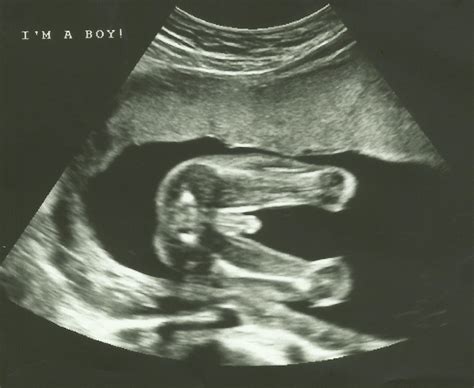

• Determining Baby's Sex: For parents who wish to know the baby's sex, the Twenty Week Scan provides a reliable indication. However, it's important to note that the accuracy of sex determination depends on the baby's position and cooperation during the scan.

Can the Twenty Week Scan determine the baby's sex?

Yes, the Twenty Week Scan can often determine the baby's sex with a high degree of accuracy. However, the baby's position and cooperation during the scan can affect the clarity of the images.